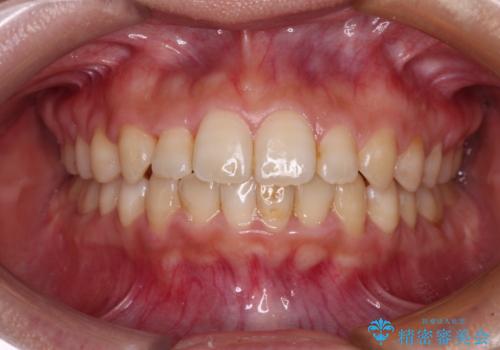

治療前にお伝えした治療期間は1~1年半でして、1年4か月の期間で終えることができました。

ワイヤー矯正は見た目や装置が当たることでの痛みを気にされる方が多いですが、月1回来院して処置をしてもらうだけで歯並びが整うため、大変お勧めです。